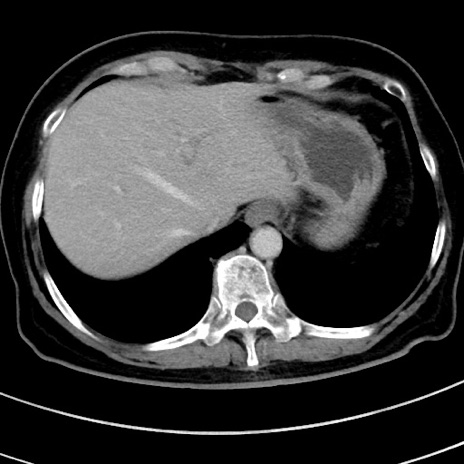

症例9(横断像)

【症例】 60歳代女性

【主訴】むかつき、みぞおちの痛み

【現病歴】3日前よりむかつきがあり、食事がとれない。

【既往歴】糖尿病

【身体所見】発熱なし、心窩部圧痛軽度あるも、腹膜刺激症状なし。

【データ】WBC 7400、CRP 1.92